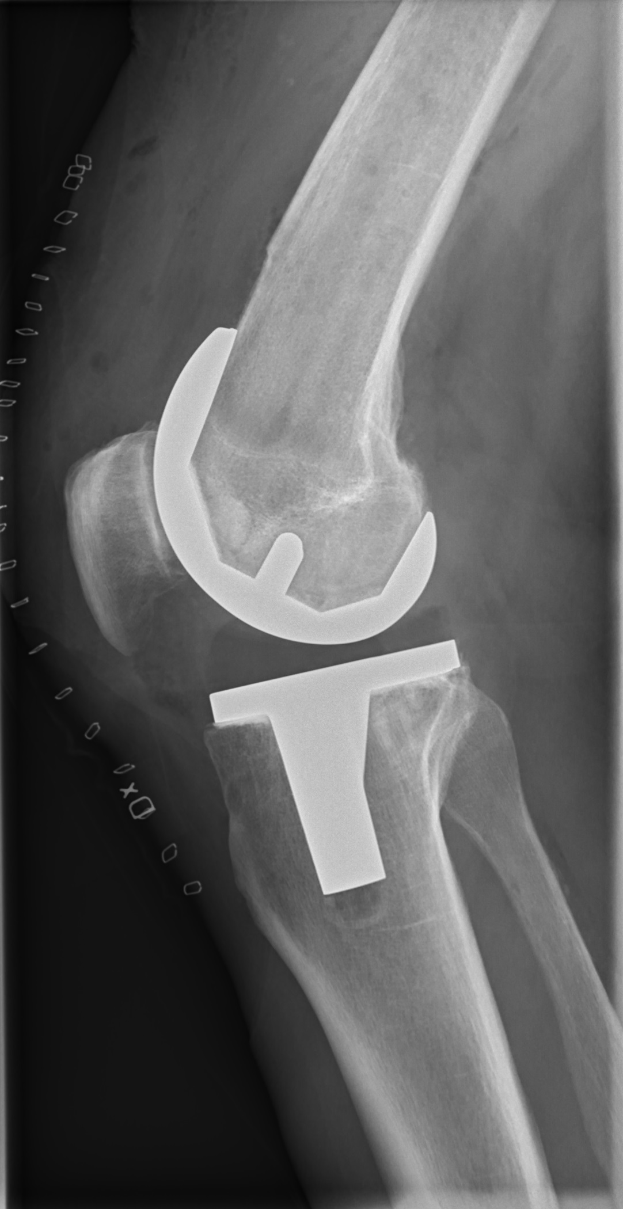

Ein Röntgenbild eines menschlichen Beins, das einen Bruch im Kniebereich zeigt, wahrscheinlich eine Bänderverletzung.Vesna Döhn

Kreuzbandriss: Saison-Aus für Düsseldorf's Schmidt - Fortuna Düsseldorf kämpft mit Verletzungspech vor dem Darmstadt-Spiel

Schmidt riss sich während einer Trainingseinheit das vordere Kreuzband. Der Verein bestätigte die Diagnose, nannte jedoch keinen Zeitrahmen für die Rückkehr. Frühere Fälle – darunter sein eigener Kreuzbandriss im Februar 2026 – deuten auf eine längere Pause hin.